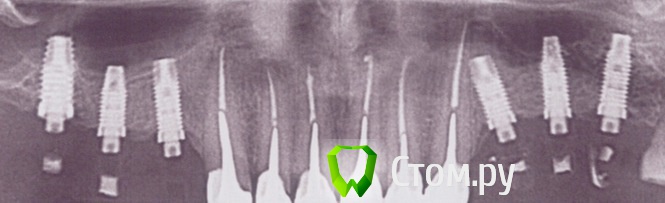

doktorSergey Опубликовано 8 мая, 2014 Поделиться Опубликовано 8 мая, 2014 Уважаемые коллеги, подскажите, пожалуйста, марку имплантатов. В системе есть временные пластиковые обтачиваемые абатменты, к винту подходит отвертка шестигранник 1.2. Ссылка на комментарий

dantist sergio Опубликовано 13 мая, 2014 Поделиться Опубликовано 13 мая, 2014 Надо выяснить в каком городе и у кого ставил! Открутить времянку,посмотреть цветовую кодировку, если есть! Напоминает биогоризонт. Ссылка на комментарий

28vs32 Опубликовано 14 мая, 2014 Поделиться Опубликовано 14 мая, 2014 нобель с внутренним трехканальным соединением(не груве) Ссылка на комментарий

Чертков Александр Опубликовано 18 мая, 2014 Поделиться Опубликовано 18 мая, 2014 нобель с внутренним трехканальным соединением(не груве)это не нобель Ссылка на комментарий

doktorSergey Опубликовано 21 мая, 2014 Автор Поделиться Опубликовано 21 мая, 2014 Опознал! Biomet 3i. Спасибо всем за помощь! Ссылка на комментарий